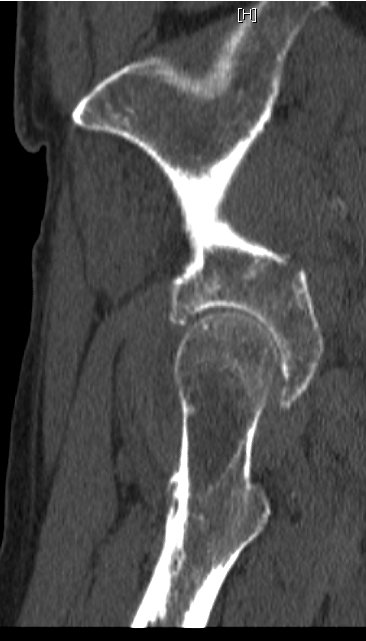

#8 Advanced disease in the thoracic spine

here and

here